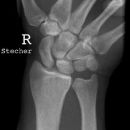

Hand / Handgelenk

Handgelenk a.p.

Beurteilungskriterien

• Neigung der distalen Radiusgelenkfläche in der Frontalebene: 15 – 35°

• Längenverhältnis Radius – Ulna: Proc.styloideus radii überragt Gelenkfläche der Ulna um 9 –12mm (<9mm Ulna-Plusvariante, >12mm Ulnaminusvariante)

• Kontinuität der drei Karpalbögen:

Proximaler Bogen: proximale Gelenkflächenkonturen von Scaphoid, Lunatum und Triquetum

Mittlerer Bogen: distale Gelenkflächenkonturen von Sacphoid, Lunatum und Triquetum

Distaler Bogen: proximale Gelenkflächenkonturen von Capitatum und Hamatum

Fehlende Abgrenzbarkeit, Versatz oder Unterbrechung sind als pathologisch zu bewerten und deuten auf eine Luxation hin.

Trapezförmige Darstellung des Lunatum in Neutralstellung? Augenzeichen des Hamulus? Superposition von Pisiforme und Triquetum? Metacarpale III in Projektion innerhalb der Radiusgelenkfläche? Lunatum zu >50% über Radiusgelenkfläche? Cave: bei Radial- oder Ulnarduktion wandert das Lunatum in umgekehrter Richtung.

• M-förmiger Verlauf der Gelenkspalten der Carpometacarpalgelenke? Luxationsstellung in den Carpometacarpalgelenken (meist dorsale Luxation)?

• Gelenkspaltweiten des Radiocarpalgelenk 2 – 2,5mm, der Carpometacarpalgelenke 1 –2mm, distales Radioulnargelenk 2mm, Gelenksspaltweiten der Intercarpalgelenke 1,5 – 2mm

Cave: SL-Dissoziation (Ruptur des SL- Bandes, häufigste Gefügestörung): Terry-Thomas-Sign = SL-Spalt > 3mm, Siegelringzeichen = Ringförmige Transparenzminderung im mittleren Scaphoiddrittel durch orthograde Projektion der Taille infolge Rotation.

• Obliteration des Scaphoidfettstreifens?

• Täuschungsmöglichkeiten durch Vielzahl akzessorischer Ossikel (abgerundete, zirkulkär-geschlossene Kortikalis), geteilte Handwurzelknochen (Scaphoid, Lunatum, Pisiforme) und Gefäßkanälchen

• Target areas leicht zu übersehender Frakturen: distales Radioulnargelenk, Processus styloideus radii et ulnae, Basen der Metacarpalia (v.a. MCP I), Hamulus.

• Grundsätzlich gilt: unklare Verhältnisse ->CT-Indikation